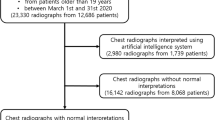

Of the 471 patients who agreed to participate in the study and provide the images and reports, the final sample for external validation of the model was 278, mainly due to computer-related issues when extracting the data. In some cases, when automatically extracting images and reports, both were not obtained, i.e., either the image was missing, or the report was missing. In addition, some reports did not include the interpretation of the image, as it was a follow-up X-ray. In these cases, the report only indicated whether or not there were changes with respect to the previous report and, therefore, they had to be discarded from the analysis (Fig. 1). Of the final sample, 144 (51.8%) obtained images without radiological abnormalities according to the radiologist's report.